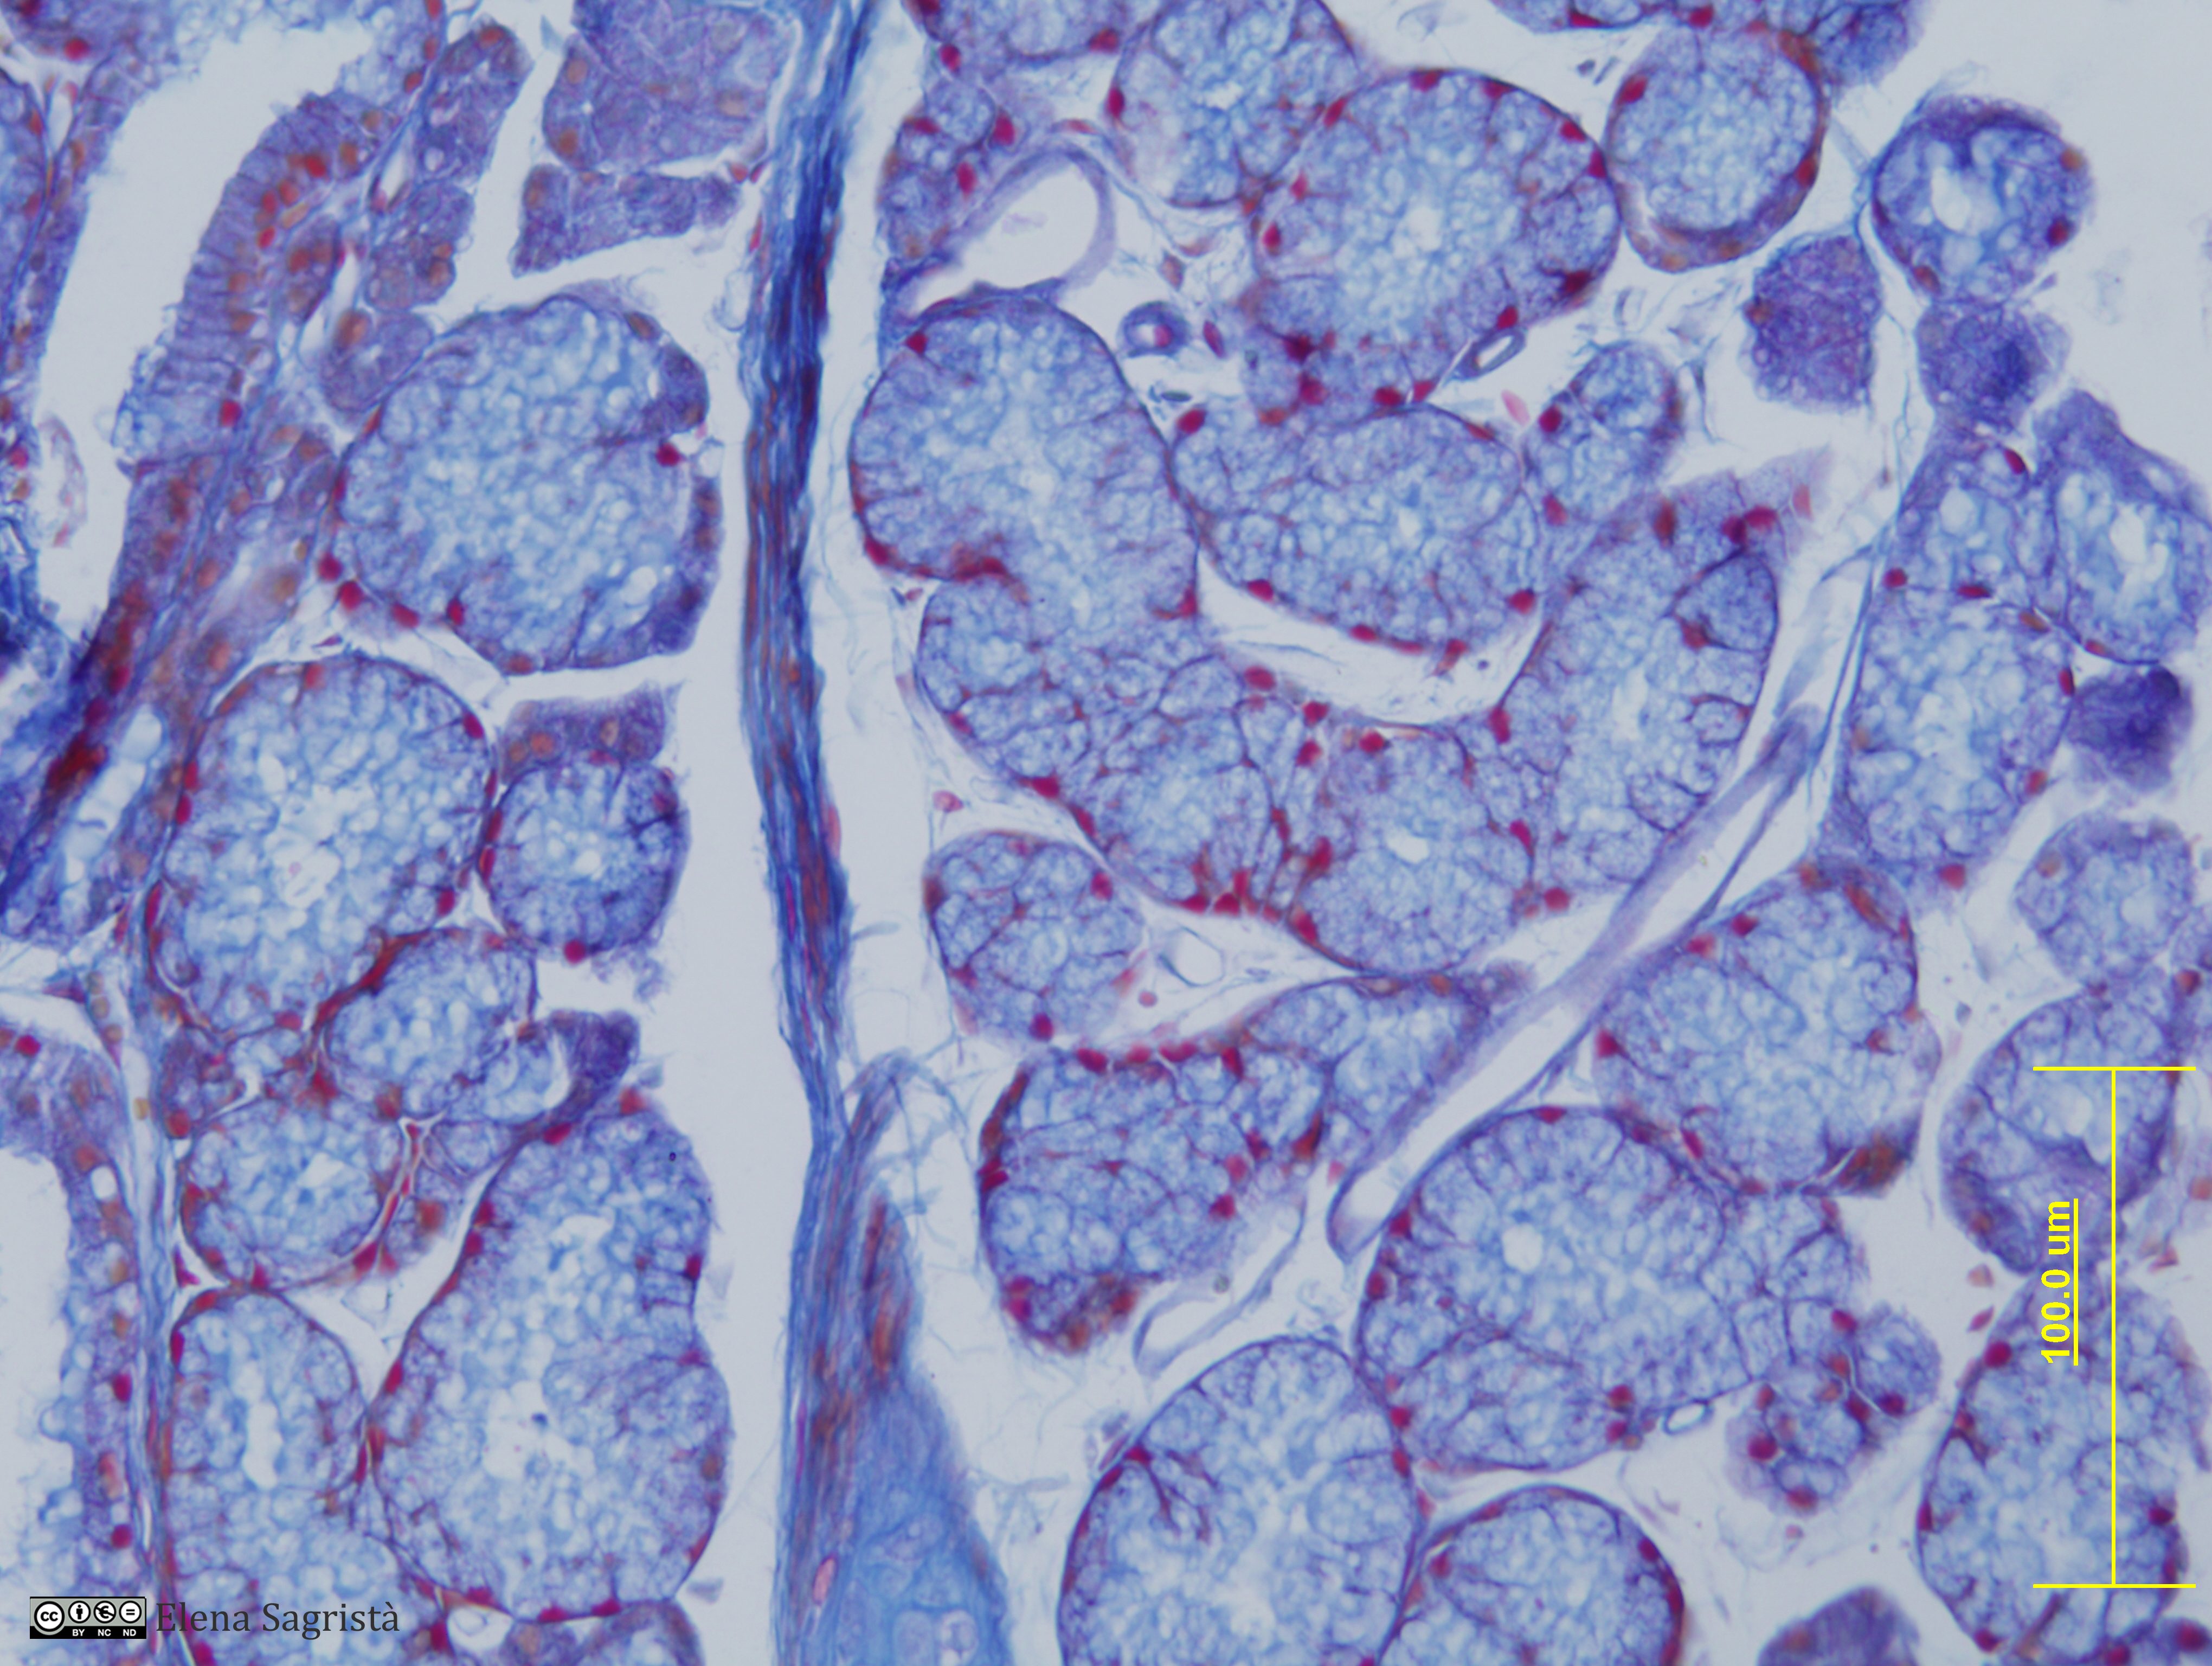

Histologia imatges: 12 Tràquea

Imatges de preparacions histològiques de Tràquea. Microscopia òptica.